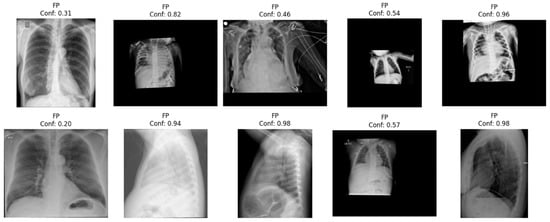

- We perform a set of experiments with models trained on multi-source data, trying to address the biases that pneumothorax models commonly suffer (chest tubes as confounder biases, label mismatch, etc.) with the aim of creating a model that is useful for clinical usage.

- Threshold optimization: To maximize clinical utility, we evaluated threshold selection strategies on the validation set. Choosing an optimal threshold is crucial, as a suboptimal choice can lead to a model that can obtain high performance metrics but no clinical utility. Our aim was to balance false negatives (which risk missed pneumothoraces and can be potentially life-threatening) and false positives (which can lead to lack of clinical confidence).